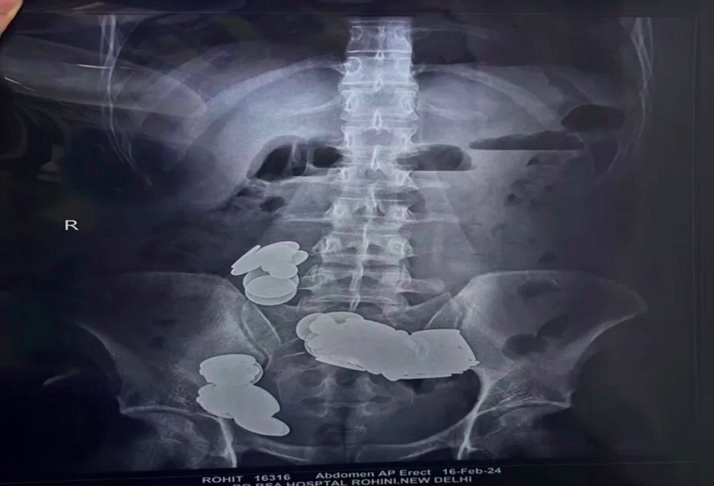

Os médicos viram que os ímãs e as moedas formaram dois grupos no intestino delgado por conta da força magnética, causando danos à parede intestinal. Foto: Reprodução/Hospital Sir Ganga Ram -

Esses objetos bloquearam o intestino, exigindo uma cirurgia de emergência para removê-los. Por sorte, os médicos conseguiram abrir o órgão e retirar todas as moedas e ímãs. Foto: Reprodução/Hospital Sir Ganga Ram -

A equipe médica removeu um total de 39 moedas (de 1, 2 e 5 rúpias) e 37 ímãs em diferentes formatos do paciente, incluindo corações, estrelas, triângulos e esferas. Foto: Reprodução/Hospital Sir Ganga Ram -